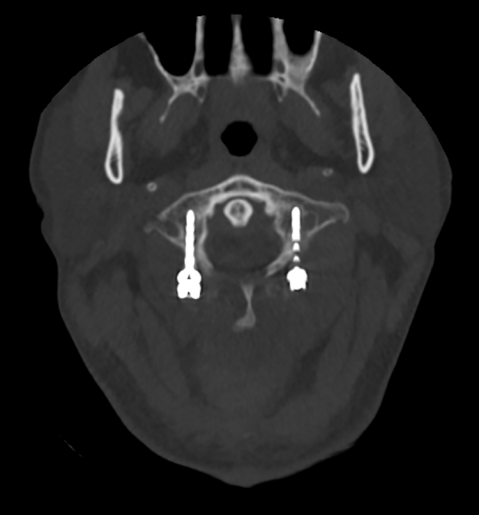

金先生伤后第7天,姜主任医师团队在麻醉手术科的密切配合下成功为他实施手术。姜主任凭借多年徒手置钉的过硬技术经验,2小时不到便完成了手术,术中出血仅100ml。术后CT显示齿状突完美复位,螺钉“不偏不倚”的位置恰到好处。术后,金先生在骨科护士长张霞芬护理团队的精心护理下,15天后伤口拆线康复出院。

第一步是先从颈椎后方入路,使用手术器械将骨折脱位复位,然后用螺钉固定;第二步是待患者恢复一段时间后再行前路手术。这个术式的难点在于强直性脊柱炎患者有严重的骨质增生表现,解剖标志不清,置钉有难度;其次,CT显示后方关节突交锁,复位困难。姜主任再次凭借多年手术经验,在二代0臂机的保驾护航下,成功地将螺钉置入椎体内,手术历经3小时。术后,金先生的右侧肢体偏瘫有了明显改善,2周后出院。